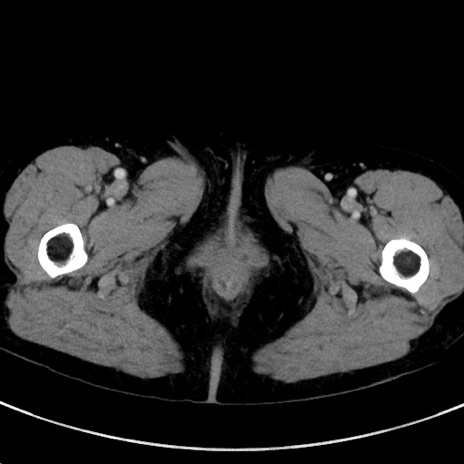

冠状断像

症例23(横断像)

【症例】70歳代女性

【主訴】下腹部痛・嘔吐

【現病歴】2日前より腹痛あり。昨日嘔吐あり。症状改善しないため来院。

【既往歴】胃GISTに対して胃部分切除後。

【身体所見】BT 37.1℃、BP 128/77mmHg、腹部:平坦・軟、下腹部に圧痛あり。

【データ】WBC 10200、CRP 0.31